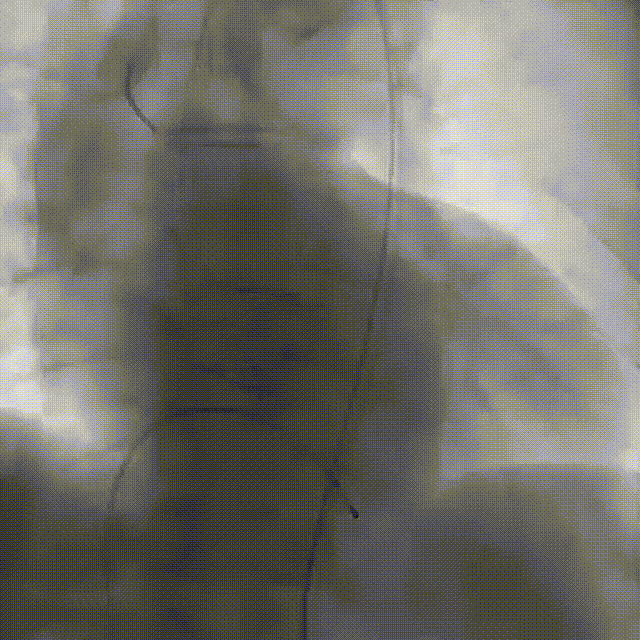

2026年伊始,TaurusTrio经导管主动脉瓣系统在武汉大学人民医院,中国科学技术大学附属第一医院,安徽医科大学第一附属医院,安徽医科大学第一附属医院北区,首都医科大学附属北京安贞医院南充医院,海南省人民医院等多家临床中心成功开展上市后全国首批植入。这不仅是TaurusTrio正式走向广泛临床应用的重要里程碑,更标志着中国单纯主动脉瓣反流介入治疗正式迈入了“心键合璧”的全新纪元。